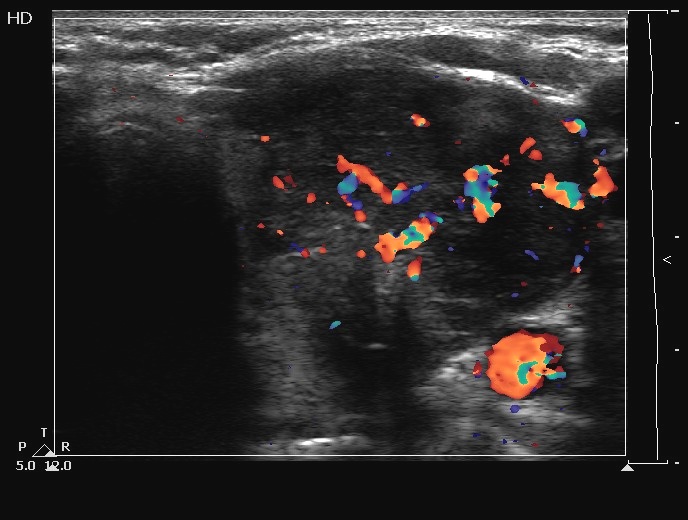

Ultrasonography. The thyroids were echonormal and contained several cystic areas and an echonormal nodule in the right lobe. There was a large partly echonormal, partly hypoechogenic nodule in the left thyroid. This lesion had irregular bordersr and presented an irregularly increased intranodular vascularization.